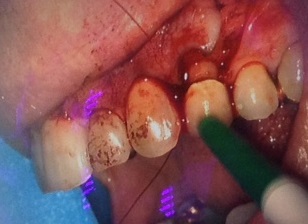

Un cas clinique: Une 24 porteuse d’un inlay core et d’une couronne céramique présente après 15 ans une lésion apicale due à une calcification du tiers apical du canal palatin incomplètement obturé. Intervention réalisée par le Dr. Guillaume Jouanny (Paris 16).

Un lambeau vestibulaire est ouvert et l’apex apparaît après nettoyage de la cavité osseuse.